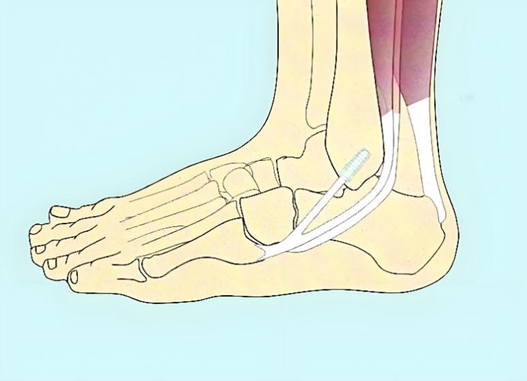

距腓前韧带位于踝关节的前外侧,起于外踝的前缘,向前内侧下方走行,止于距骨颈的外侧缘,外观呈现平行四边形,对维持踝关节的稳定性至关重要。

图2:踝关节前侧解剖

图3:踝关节外侧韧带解剖:①距腓前韧带;②跟腓韧带;③颈韧带;④骨间韧带;⑤下胫腓前韧带

图4:距腓前韧带的解剖位置的局部放大图,绿色部分为距腓前韧带